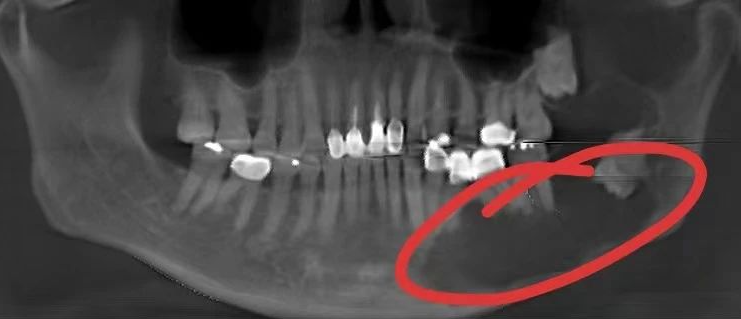

33岁女,根尖周囊肿、牙源性上颌窦炎

(李延超医生提供)

33岁女患者,四年前曾做根管治疗。一个月前,左上颌反复肿胀疼痛,从外院转入我院口腔颌面外科,诊断为“根尖周囊肿、牙源性上颌窦炎”,由口腔颌面外科主治医师李延超主刀,一次性切除了囊肿和上颌窦的炎症组织。